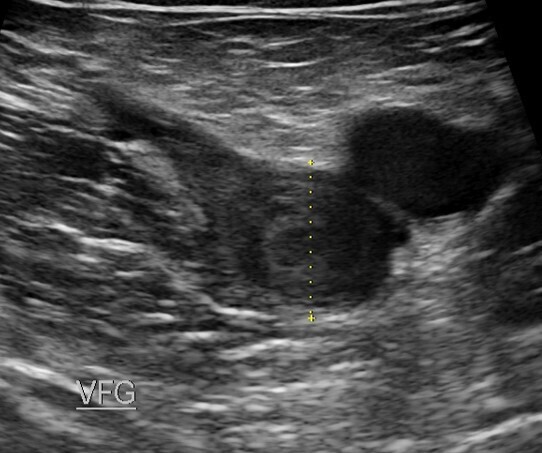

Que nous dit la VRAIE VIE sur les TVP ?

Dès lors que le patient est anticoagulé efficacement et porte sa compression médicale de classe 2 (classe 3 peu utilisable et en plus non portée), les patients doivent marcher. Il s'agit d'une marche chaque jour de 4000 à 6000 pas. Cependant il faut expliquer aux patients les bienfaits de la marche.

La localisation sus-inguinale, thrombose iliaque, voire ilio-fémorale est à l'origine d'une gêne à la marche avec un retentissement sur la qualité de vie , c'est attendu.

Les thromboses proximales, notamment iliaques, sont sur le plan de l'hémodynamique veineuse un obstacle majeur, surtout dans les premiers jours, car la circulation collatérale de suppléance (sus-pubienne) met 15 jours pour se développer. Ceci n'est pas le cas des TVP fémoro-poplitées où les réseaux de suppléance saphéniens sont activés immédiatement. De plus cette obstruction iliaque génère une hypertension veineuse ++++

La marche active quotidienne est vivement recommandée (depuis maintenant 20 ans) avec une compression de classe 2 le plus tôt possible, à la "dose" de 45 mn/jour.

La marche stimule la reperméabilisation du thrombus et à un effet antalgique et anti-oedème.

La marche a un retentissement bénéfique à la fois sur la qualité de vie et sur le stress post-TVP qui n'est pas rare.